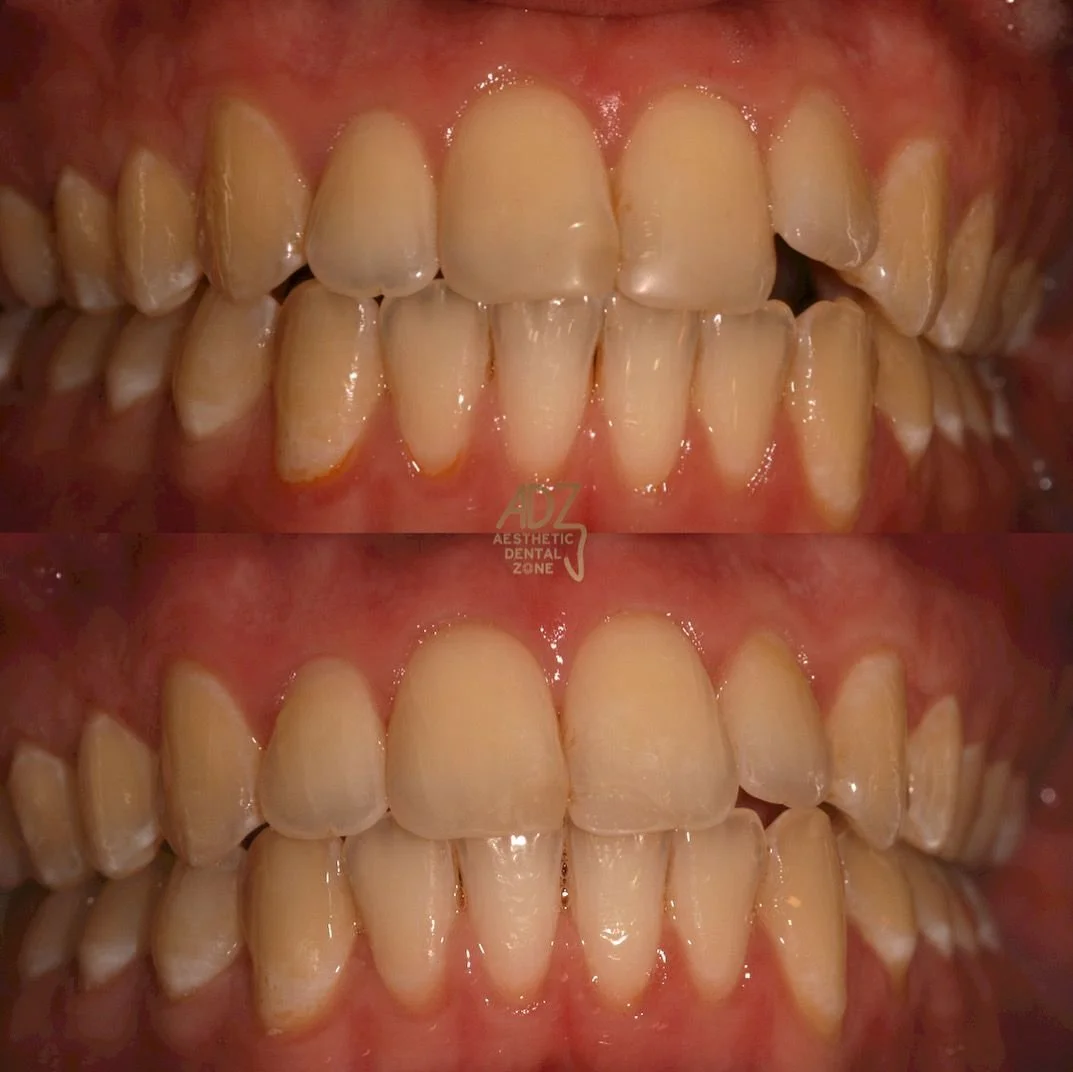

Orthodontics is the dentistry branch that focuses on correcting the alignment of a patient’s teeth and jaws. If you’re feeling self-conscious and anxious about your crooked smile, don’t worry! Not everyone has natural and perfect teeth, but thanks to our orthodontics, you can have the smile you have always wanted!

Looking for an alternative to metal braces? Here at Aesthetic Dental Zone, we offer Clear Aligner or also known as Invisalign. A simple and invisible cosmetic solution to achieving the smile you desire. Avoid fixed appliances (braces) and realign your teeth with a set of our aligners. They are comfortable, clear and easy to wear.